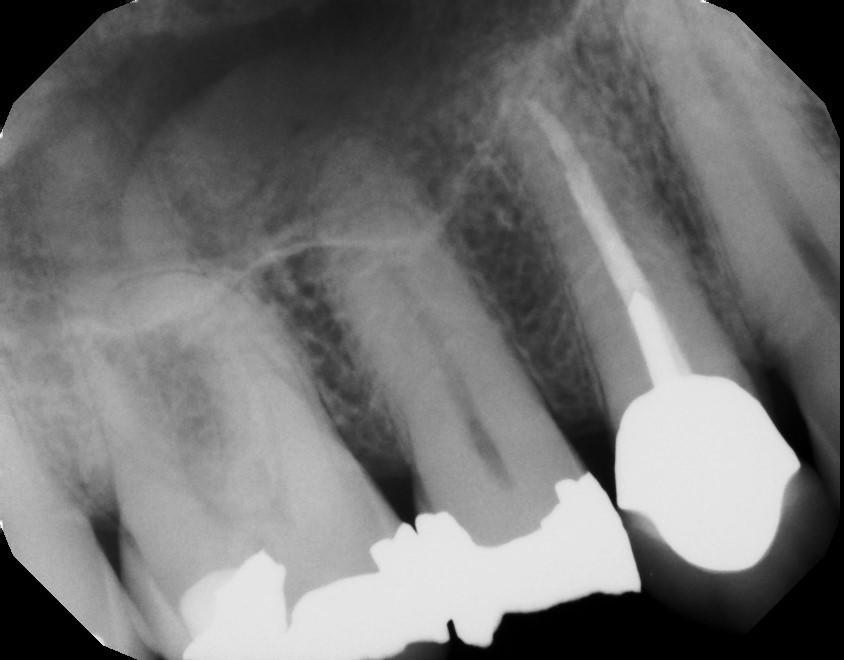

We love using our MouthWatch intra oral camera to document for our patients! We will often use this tool during your appointments to capture an image of older fillings to monitor breakdown, or any other area of the mouth that we want to watch at your next appointment. In this case, our patient came in with a broken tooth caused by an older silver filling, we were able to take an X-Ray of the area along with an intraoral photo to ensure that they received the best next steps for their treatment plan!